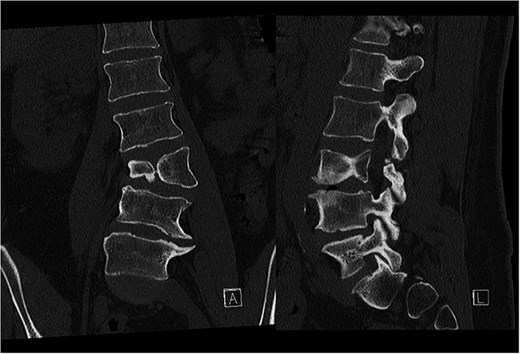

Preoperative CT demonstrating L3 hemivertebra; anteroposterior view (A) on the left side of the image, and lateral view (L) on the right side of the image.

A 43-year-old female with a history of a previous isolated right-sided L3 foraminotomy at an external facility (this intervention temporarily alleviated her leg pain but exacerbated her back pain) was referred to our institution due to chronic back pain, right-sided leg pain without neurological dysfunction, and a forward-leaning posture, which was correctable with verbal cues. The back pain, in the absence of neurological deficits, began 13 years prior, at which time she was diagnosed with adult congenital scoliosis caused by L3 hemivertebrae (Figs 1 and 2). Imaging confirmed a L3 hemivertebra resulting in a 24° Cobb angle of congenital scoliosis (Fig. 1), without associated cord abnormalities on MRI.